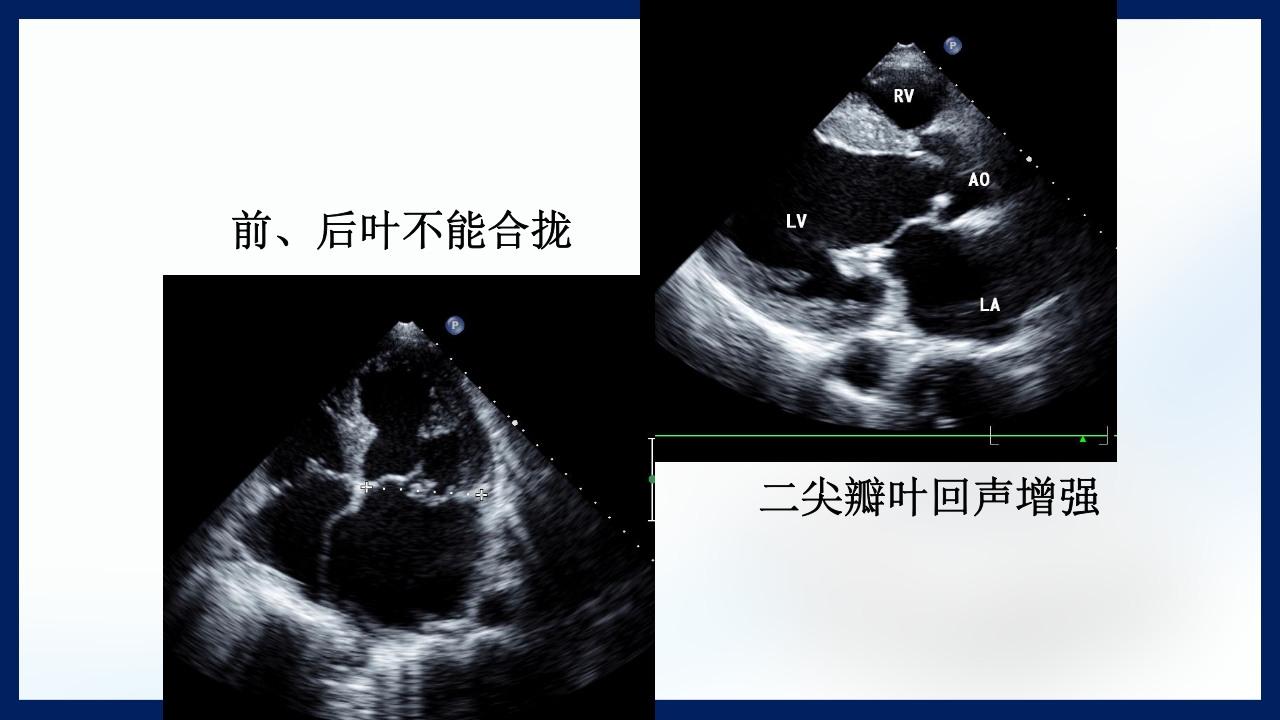

心 脏 瓣膜 医师:XXX 日期:20XX.XX.XX 讲授目的和要求 1 掌握二尖瓣和主动脉瓣膜病变的病理生理、临床表现及诊断方法。 熟悉二尖瓣和主动脉瓣膜病变的病因、鉴别诊断、并发症、治疗原则及 2 手术适应证。 3 了解瓣膜病的检查方法及治疗新进展。 心脏瓣膜病 是由于炎症、粘液样变性、退行性改变等原 因引起的单个或多个瓣膜结构的功能或结构异常,导致 瓣口狭窄及(或)关闭不全。二尖瓣最常受累,其次为 主动脉瓣。 (Rheumatic Heart Disease)简称风心病, 是风湿性炎症过程所致瓣膜损害,主要累及40岁以下人 群。 瓣膜粘液样变性和老年瓣膜钙化所致瓣膜病日渐增多。 3 瓣膜病分类 按病因分类: 风湿性、老年退行性、先天性、相对性 按受累部位和类型分: 二尖瓣狭窄、二尖瓣关闭...